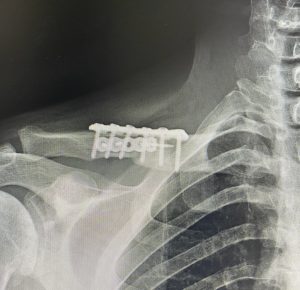

I don’t think the question is whether a secondary clavicle reduction can be done but how much more could actually be safely achieved in terms of the clavicle bone removal. In looking at your postoperative x-ray you have a significant size match difference between the inner and outer clavicle bone egments that have been brought back together. While every clavicle reduction patient has a mismatch between the sizes of the two bone ends yours is particularly impressive. While we assume that has gone on to successfully healing, and this is where a long-term postoperative x-ray would be helpful, the very relevant question is if that size mismatch is challenged again would it go on to successful healing like it did the first time. That is the gamble that we take and I am fairly certain the risks of a nonunion the second time would definitely be higher than the first time.